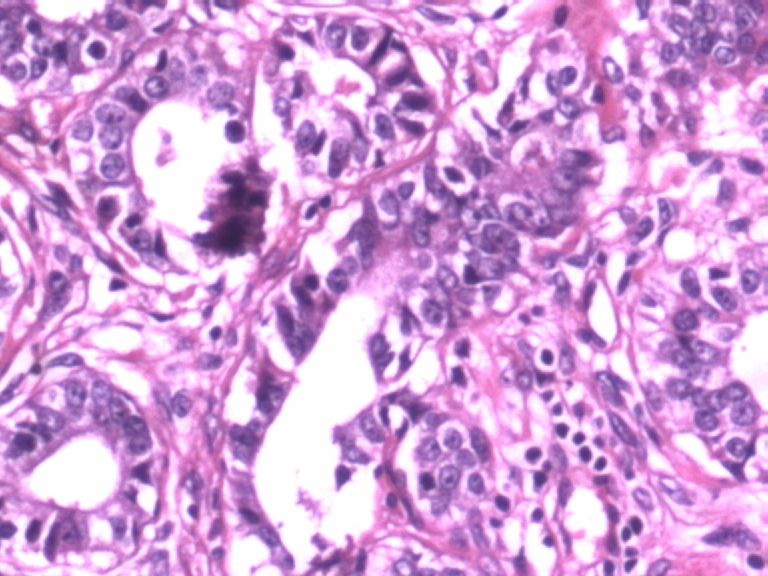

• 乳腺肿物图4

图4

患者,女,29岁,右侧乳腺肿物一个月。切面淡黄,均匀一致,质中。

标签:乳腺管状腺瘤

病变组织小叶结构未见,见管状、盲管状的腺管,周围似有空亮的肌上皮,腺上皮可见细小的核仁,染色质均细,导管上皮普通型增生。有包膜为盲管状腺瘤,则为腺病。

无则为腺病

有肌上皮而且有的地方还有肌上皮增生,应该是腺病,你应该多采些低倍镜的图像,高倍镜的大多了没有太大的意义。